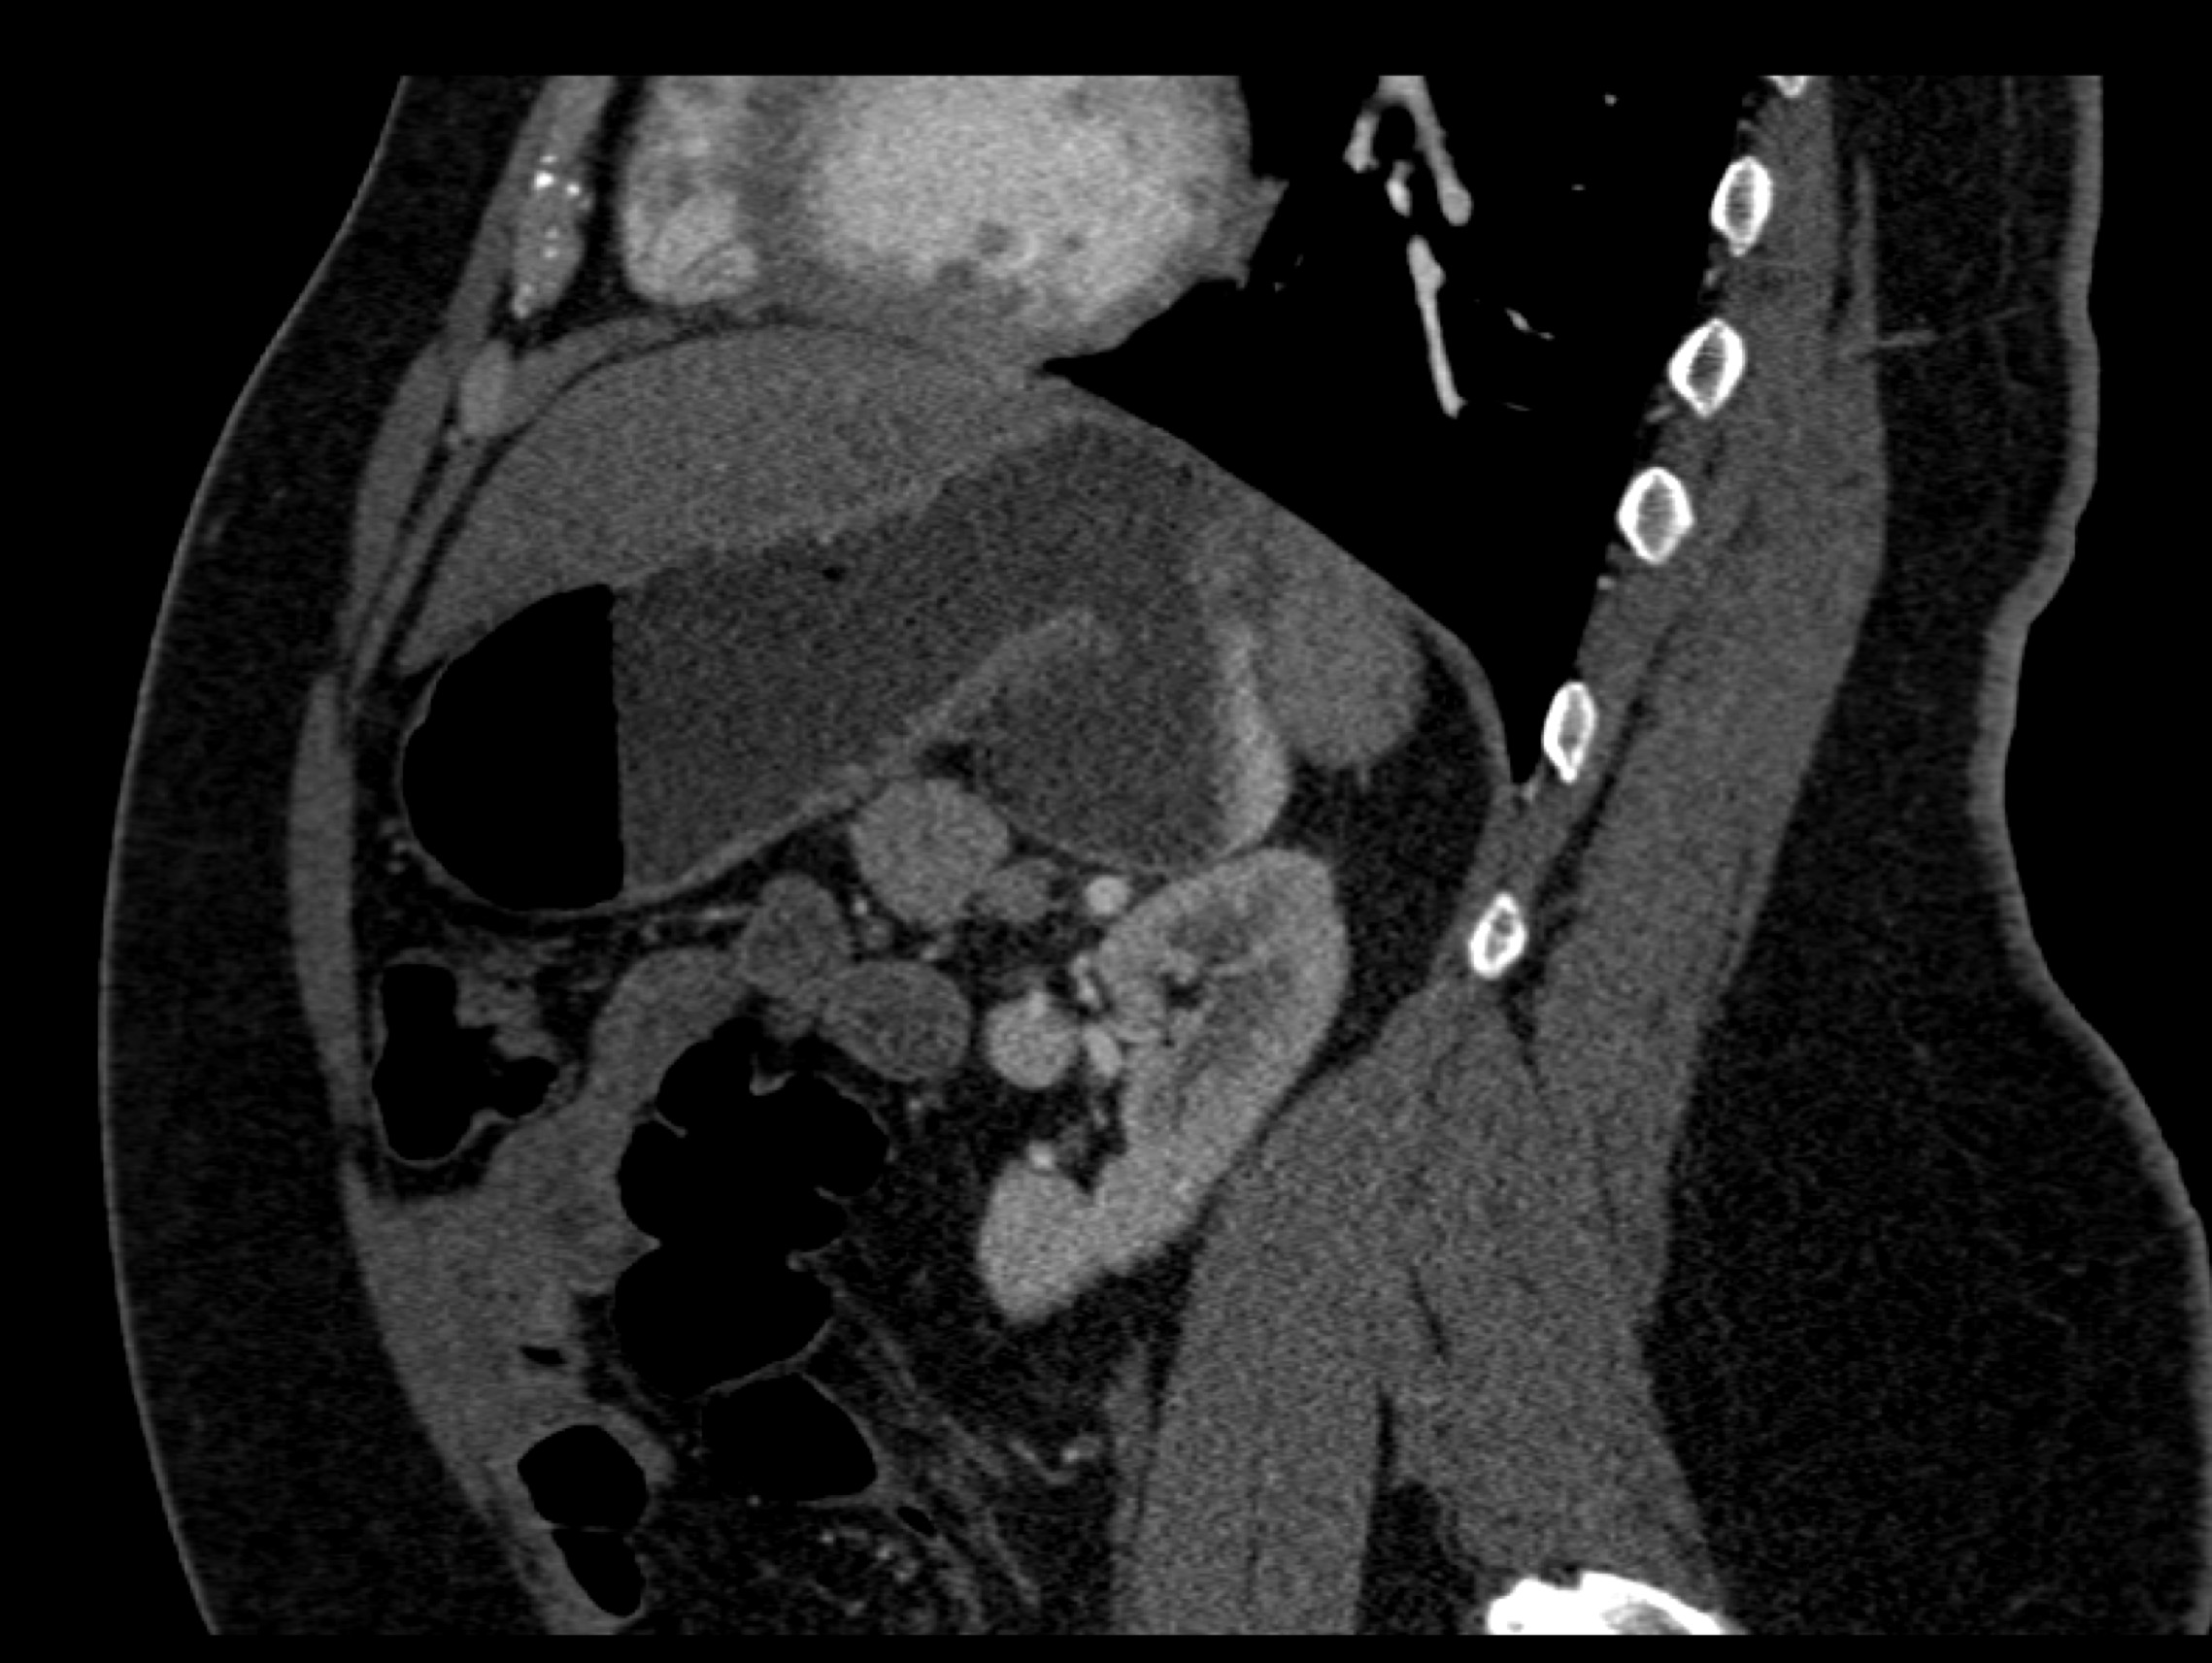

8) The most likely diagnosis in this case is?

clear cell renal cell carcinoma

large B-cell lymphoma

seminoma

renal abscess